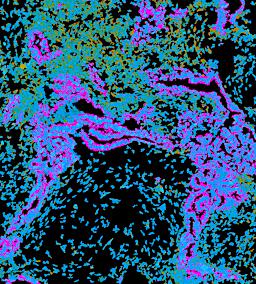

Pancreatic ductal adenocarcinoma is a lethal disease with limited treatment options and poor survival. We studied 83 spatial samples from 31 patients (11 treatment-naïve and 20 treated) using single-cell/nucleus RNA sequencing, bulk-proteogenomics, spatial transcriptomics and cellular imaging. Subpopulations of tumor cells exhibited signatures of proliferation, KRAS signaling, cell stress and epithelial-to-mesenchymal transition. Mapping mutations and copy number events distinguished tumor populations from normal and transitional cells, including acinar-to-ductal metaplasia and pancreatic intraepithelial neoplasia. Pathology-assisted deconvolution of spatial transcriptomic data identified tumor and transitional subpopulations with distinct histological features. We showed coordinated expression of TIGIT in exhausted and regulatory T cells and Nectin in tumor cells. Chemo-resistant samples contain a threefold enrichment of inflammatory cancer-associated fibroblasts that upregulate metallothioneins. Our study reveals a deeper understanding of the intricate substructure of pancreatic ductal adenocarcinoma tumors that could help improve therapy for patients with this disease.